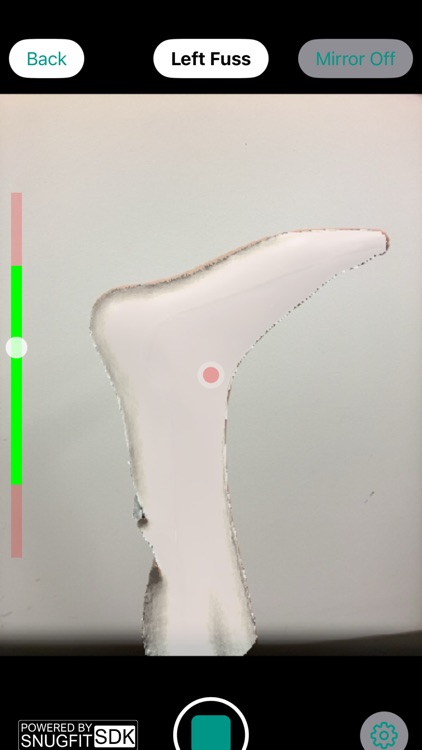

Die Springer 3D-App ist für medizinisches Fachpersonal konzipiert, um einen 3D-Scan Ihrer Körperteile (z. B. Fuß, Knie usw.) zu erfassen und individuelle Orthesen und Prothesen über Springer zu bestellen. Das Bestellformular und die Scanmodalität in der App sind einzigartig bei Springer in Berlin.

Die Springer 3D-App ist für medizinisches Fachpersonal konzipiert, um einen 3D-Scan Ihrer Körperteile (z. B. Fuß, Knie usw.) zu erfassen und individuelle Orthesen und Prothesen über Springer zu bestellen. Das Bestellformular und die Scanmodalität in der App sind einzigartig bei Springer in Berlin.

The Springer 3D app is designed for healthcare professionals to capture a 3D scan of your body parts (e.g. foot, knee etc.) for ordering custom orthotics and prosthetics through Springer. The ordering form and scan modality in the app is unique to Springer in Berlin.